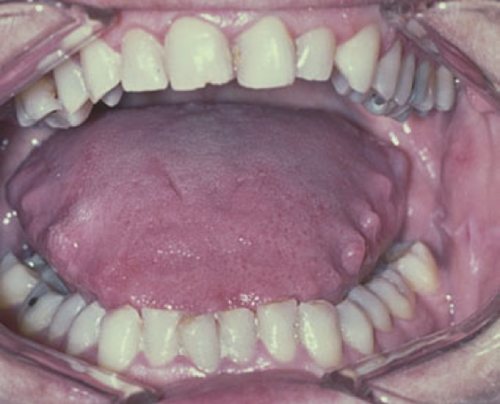

Локализация отпечатков может отмечаться в разных участках языка – по бокам и у корня. Производится оценка, имеется ли налёт из грибковых бактерий, отёки, трещины, язвы. Проявления вызваны патологиями ЖКТ, нервной системы, ротовой полости, дыхательного аппарата.

Причиной образования отпечатков зубов на мышечном органе становится его опухание и увеличение в размере, что выступает симптомом недуга. Причин подобного явления множество, это усложняет постановку диагноза, поэтому опухание языка нельзя упускать из виду.

При этом воспалительном заболевании на языке образуются характерные отверстия. Также одним из распространенных симптомов этой болезни является сглаживание сосочков. Язык приобретает гладкую блестящую поверхность. Также заболевание сопровождается отеками органа, болезненными ощущениями. Иногда могут образовываться пятна или неприятный запах.

Клиническая картина проходит следующим образом. Во время употребления пищи больной ощущает сильную боль и жжение. Если образовалась инфекция, то могут появляться язвы с некрозом. В таком состоянии пациент быстро теряет силы и ослабевает. Из-за воспалительных процессов и язв образуется отечность, которая приводит к тому, что на языке остаются отпечатки зубов.

Образование отчетливых отпечатков зубов на языке часто сопровождается наличием налета. Состоит он из грибковых бактерий, мертвых клеток кожи и микрочастиц пищи. Чем толще слой налета, тем больше теряется вкусовых рецепторов.

В совокупности эти два симптома могут говорить о ряде заболеваний. Самыми распространенными являются невроз и нарушение пищеварительной системы. При осмотре пациента врачом могут быть обнаружены маленькие пузырьки на кончике языка. Это говорит о проблемах с органами дыхания. Также подобные симптомы встречаются у больных сердечно-сосудистыми заболеваниями.

Мышечный орган во рту здорового человека обладает розоватым цветом, гладкой поверхностью. Также присутствует тонкий слой налёта, под которым хорошо заметы сосочки, что делает его похожим на бархат. Чем толще слой налёта, тем больше теряется вкусовых рецепторов.

При сбоях в организме может начаться отечность мышечного органа. Как правило, это свидетельствует о хроническом гастрите. Именно тогда у больных появляются отпечатки зубов на языке по краям.